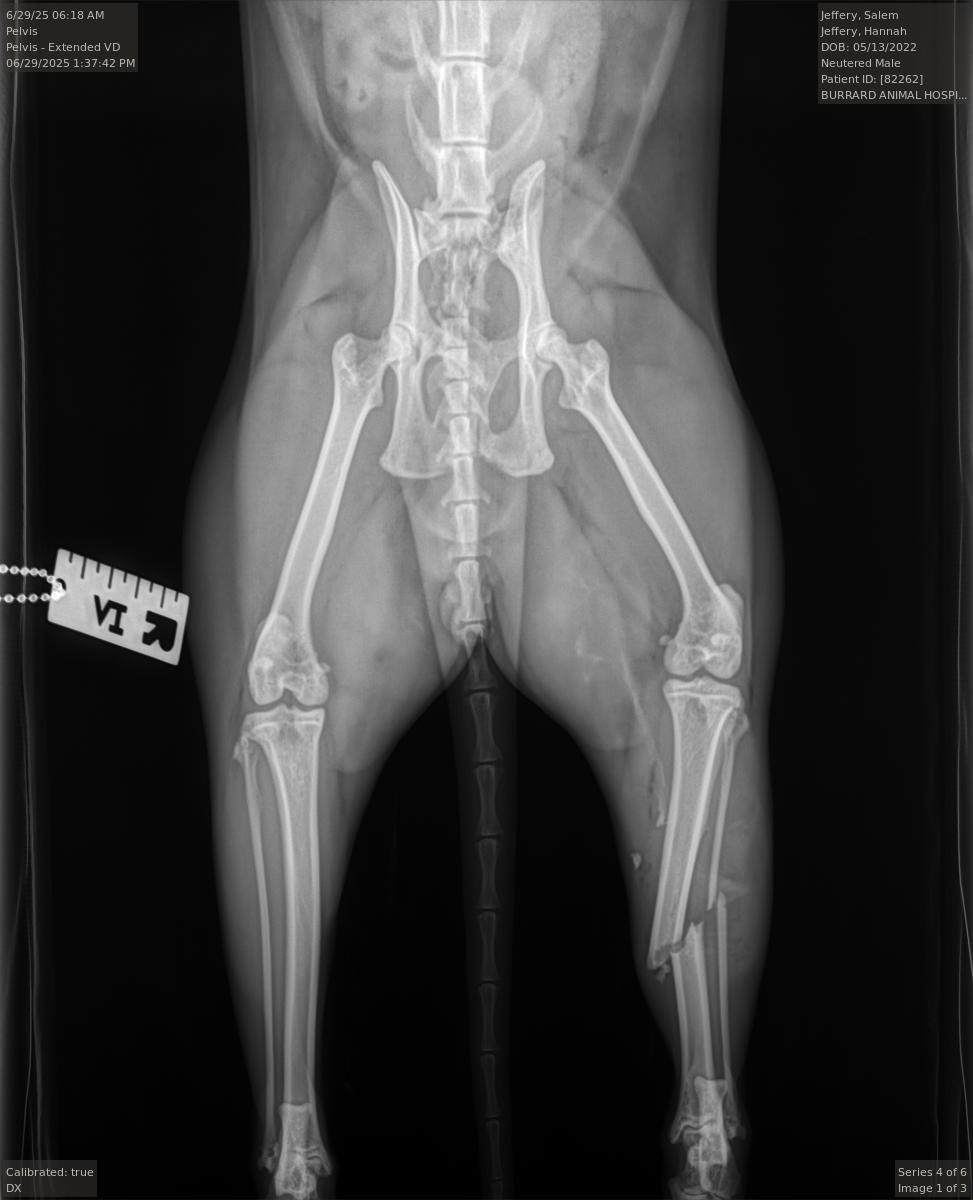

Hi, my name is Teresa and I’m creating this fundraiser on behalf of my daughter Hannah and her sweet, special cat Salem. On the evening of June 28th, Salem fell 5 stories from a window that was unknowingly left open by someone. He was rushed to the hospital immediately. They have confirmed a fractured tibia and fibula, lung contusions, and trauma on the liver, with further testing and evaluation to be done.